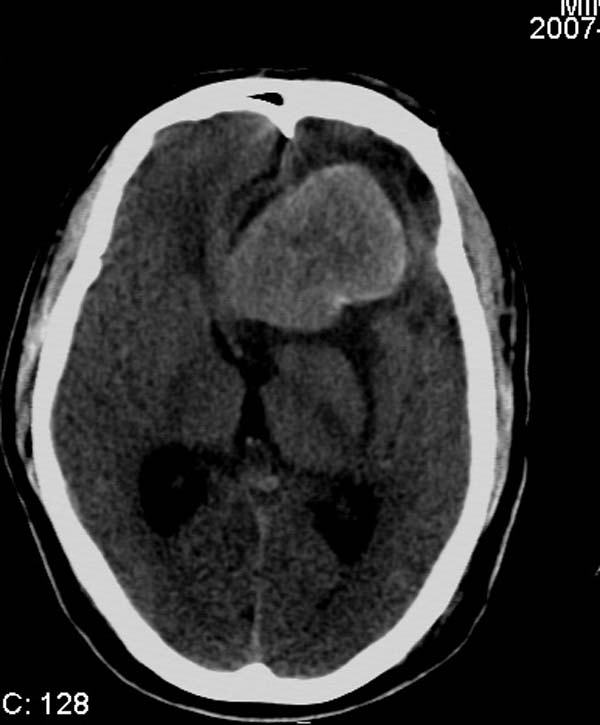

以下是引用拾荒者在2007-10-5 19:31:00的发言:[br]左额叶镰旁不规则形高密度影,中间见钙化灶及略低密度影,占位征象明显,周围有低密度水肿带环绕,首先考虑脑膜瘤。